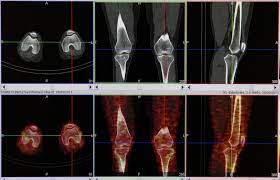

scintigraphie articulaire du genou

Publié par : radiologia academy